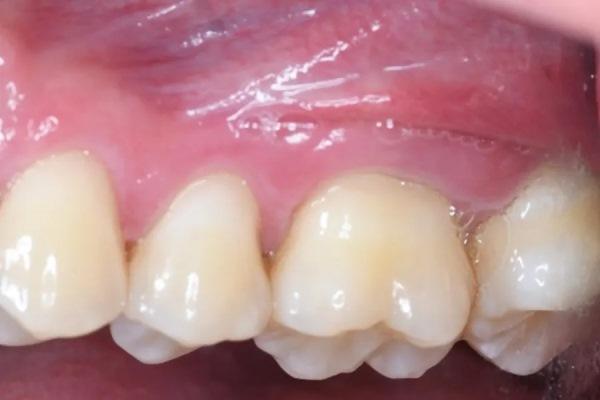

Фото 1 и Фото 2. Внеоральный осмотр выявил легкую болезненность в левом ВНЧС; интраоральный осмотр показал тонкий фенотип десны, локализованную рецессию десны и потерю клинического прикрепления. Предоперационные вестибулярный (Фото 1) и окклюзионный (Фото 2) виды показали воспаление десны, минимальную рецессию и глубину зондирования 12 мм с вестибулярной поверхности зуба № 2.6.